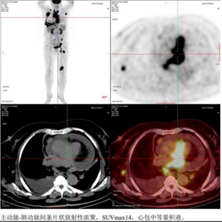

2024年12月16日起,行西达本胺联合R2-CHOP方案一线治疗(西达本胺20mg d1/4/8/11口服;利妥昔单抗700mg d0;环磷酰胺1.35g d1;脂质体阿霉素60mg d1;长春新碱2mg d1;地塞米松15mg d1-5;来那度胺25mg d1-14),21天为一周期。4周期后(2025年3月6日)PET-CT评估示原膈肌上下多发高代谢淋巴结及结外病灶体积明显缩小或消失,代谢明显减低。原右眼眶内、右侧胸壁、右侧胸膜、心包病灶,较前明显体积缩小,代谢恢复正常。Deauville评分2分,疗效评估达CR。

图片

2025-03 PET-CT检查提示达完全缓解